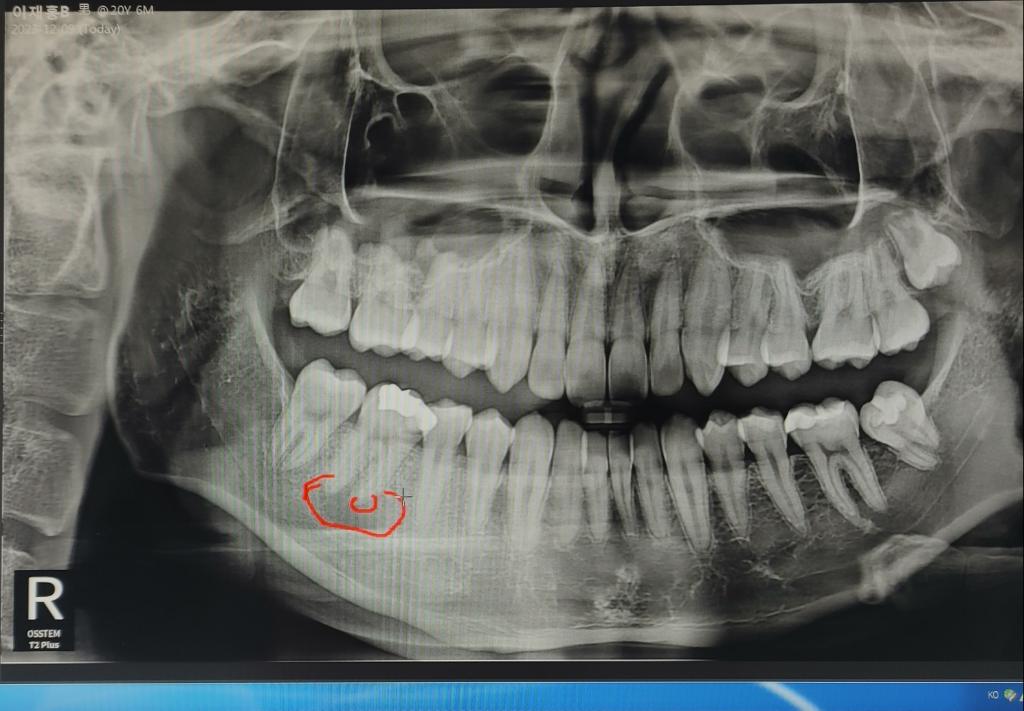

잇몸이 아파서 치과갔더니 염증이 저만큼 있다고 하는데

뿌리끝에 저렇게 염증이 잇다면 일단 신경치료를 하셔야될것같습니다. 보통 신경치료는 3-4번 받아야되지만 뿌리끝 염증이 잇다면 시간이 더 오래 걸릴수도 잇을것같습니다 .

치근단 질환은 치아안의 치수강에 감염이 되어서 생기게 됩니다.

치수안의 감염물질을 제거하면 3개월 정도 지나면서 점차 치유되게 되는데 신경치료는 가능하면 한곳에서 받는것이 좋습니다.